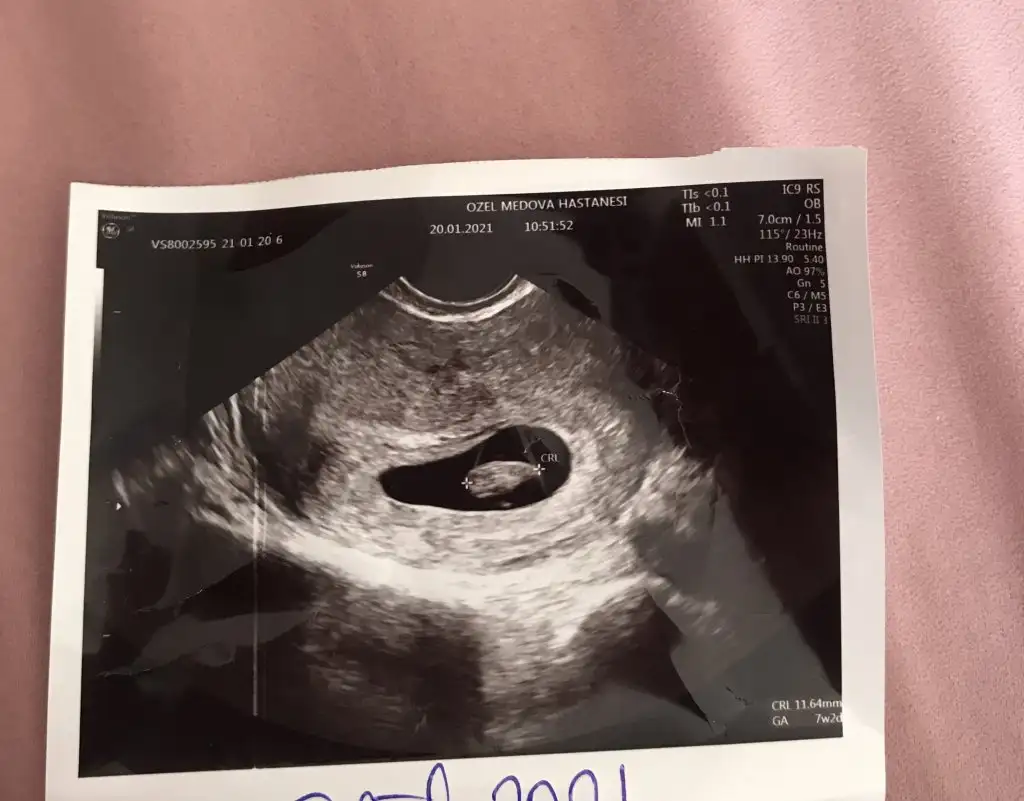

Kız tabiki en iyi 11 12 13 haftalar olmalıIkra meyra banada kesenden tahminde bulunabilir misin. Vajinal bakıldı ilki 6. Hafta ikincisi 7. Hafta.Biliyorum çok erken ama tecrübelerine dayanarak tahminde bulunursan sevinirim.

Emin olamadim kız gibi sanki başka USG varsa paylaşınMerhabaIkra meyra bana da bakmanız mümkün mü acaba hem 11+3 hem 12+1 haftalık resimleri attım